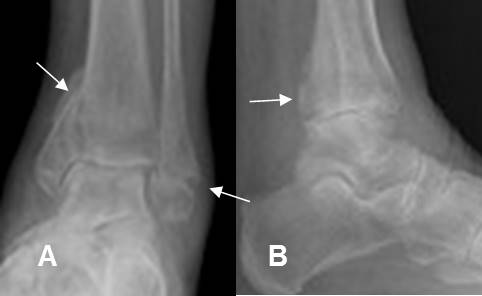

Fig 181. Fractura de Cotton.

A: Rx AP y B: Rx lateral. Fractura trimaleolar, con compromiso de ambos maleolos y la parte posterior de la tibia.